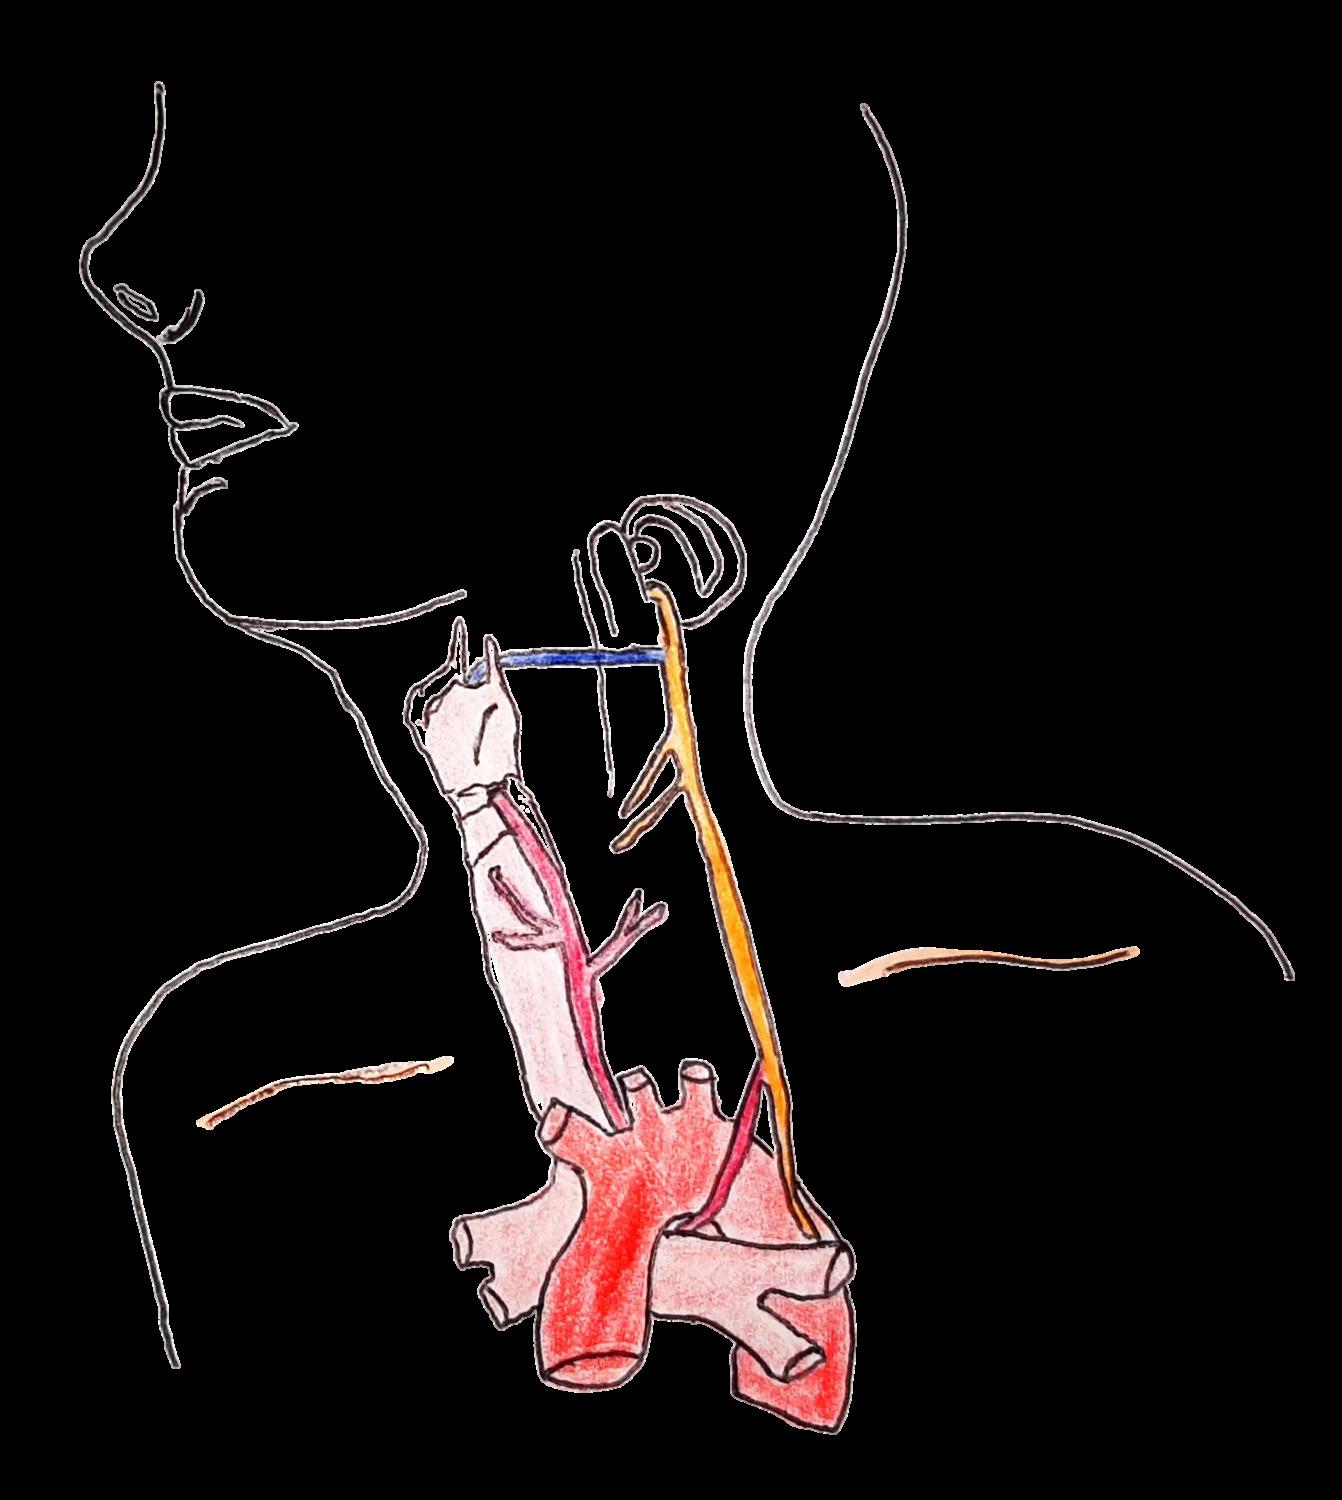

NERVIO VAGO (X PAR)

CARACTERÍSTICAS:

Regula los latidos del corazón Controla el movimiento muscular Mantiene la respiración. Es responsable de mantener el tracto digestivo en buen funcionamiento.

Laringe

Nervio laríngeo recurrente izquierdo

Arco aórtico

Nervio laríngeo superior

NERVIO VAGO

Raíz craneal